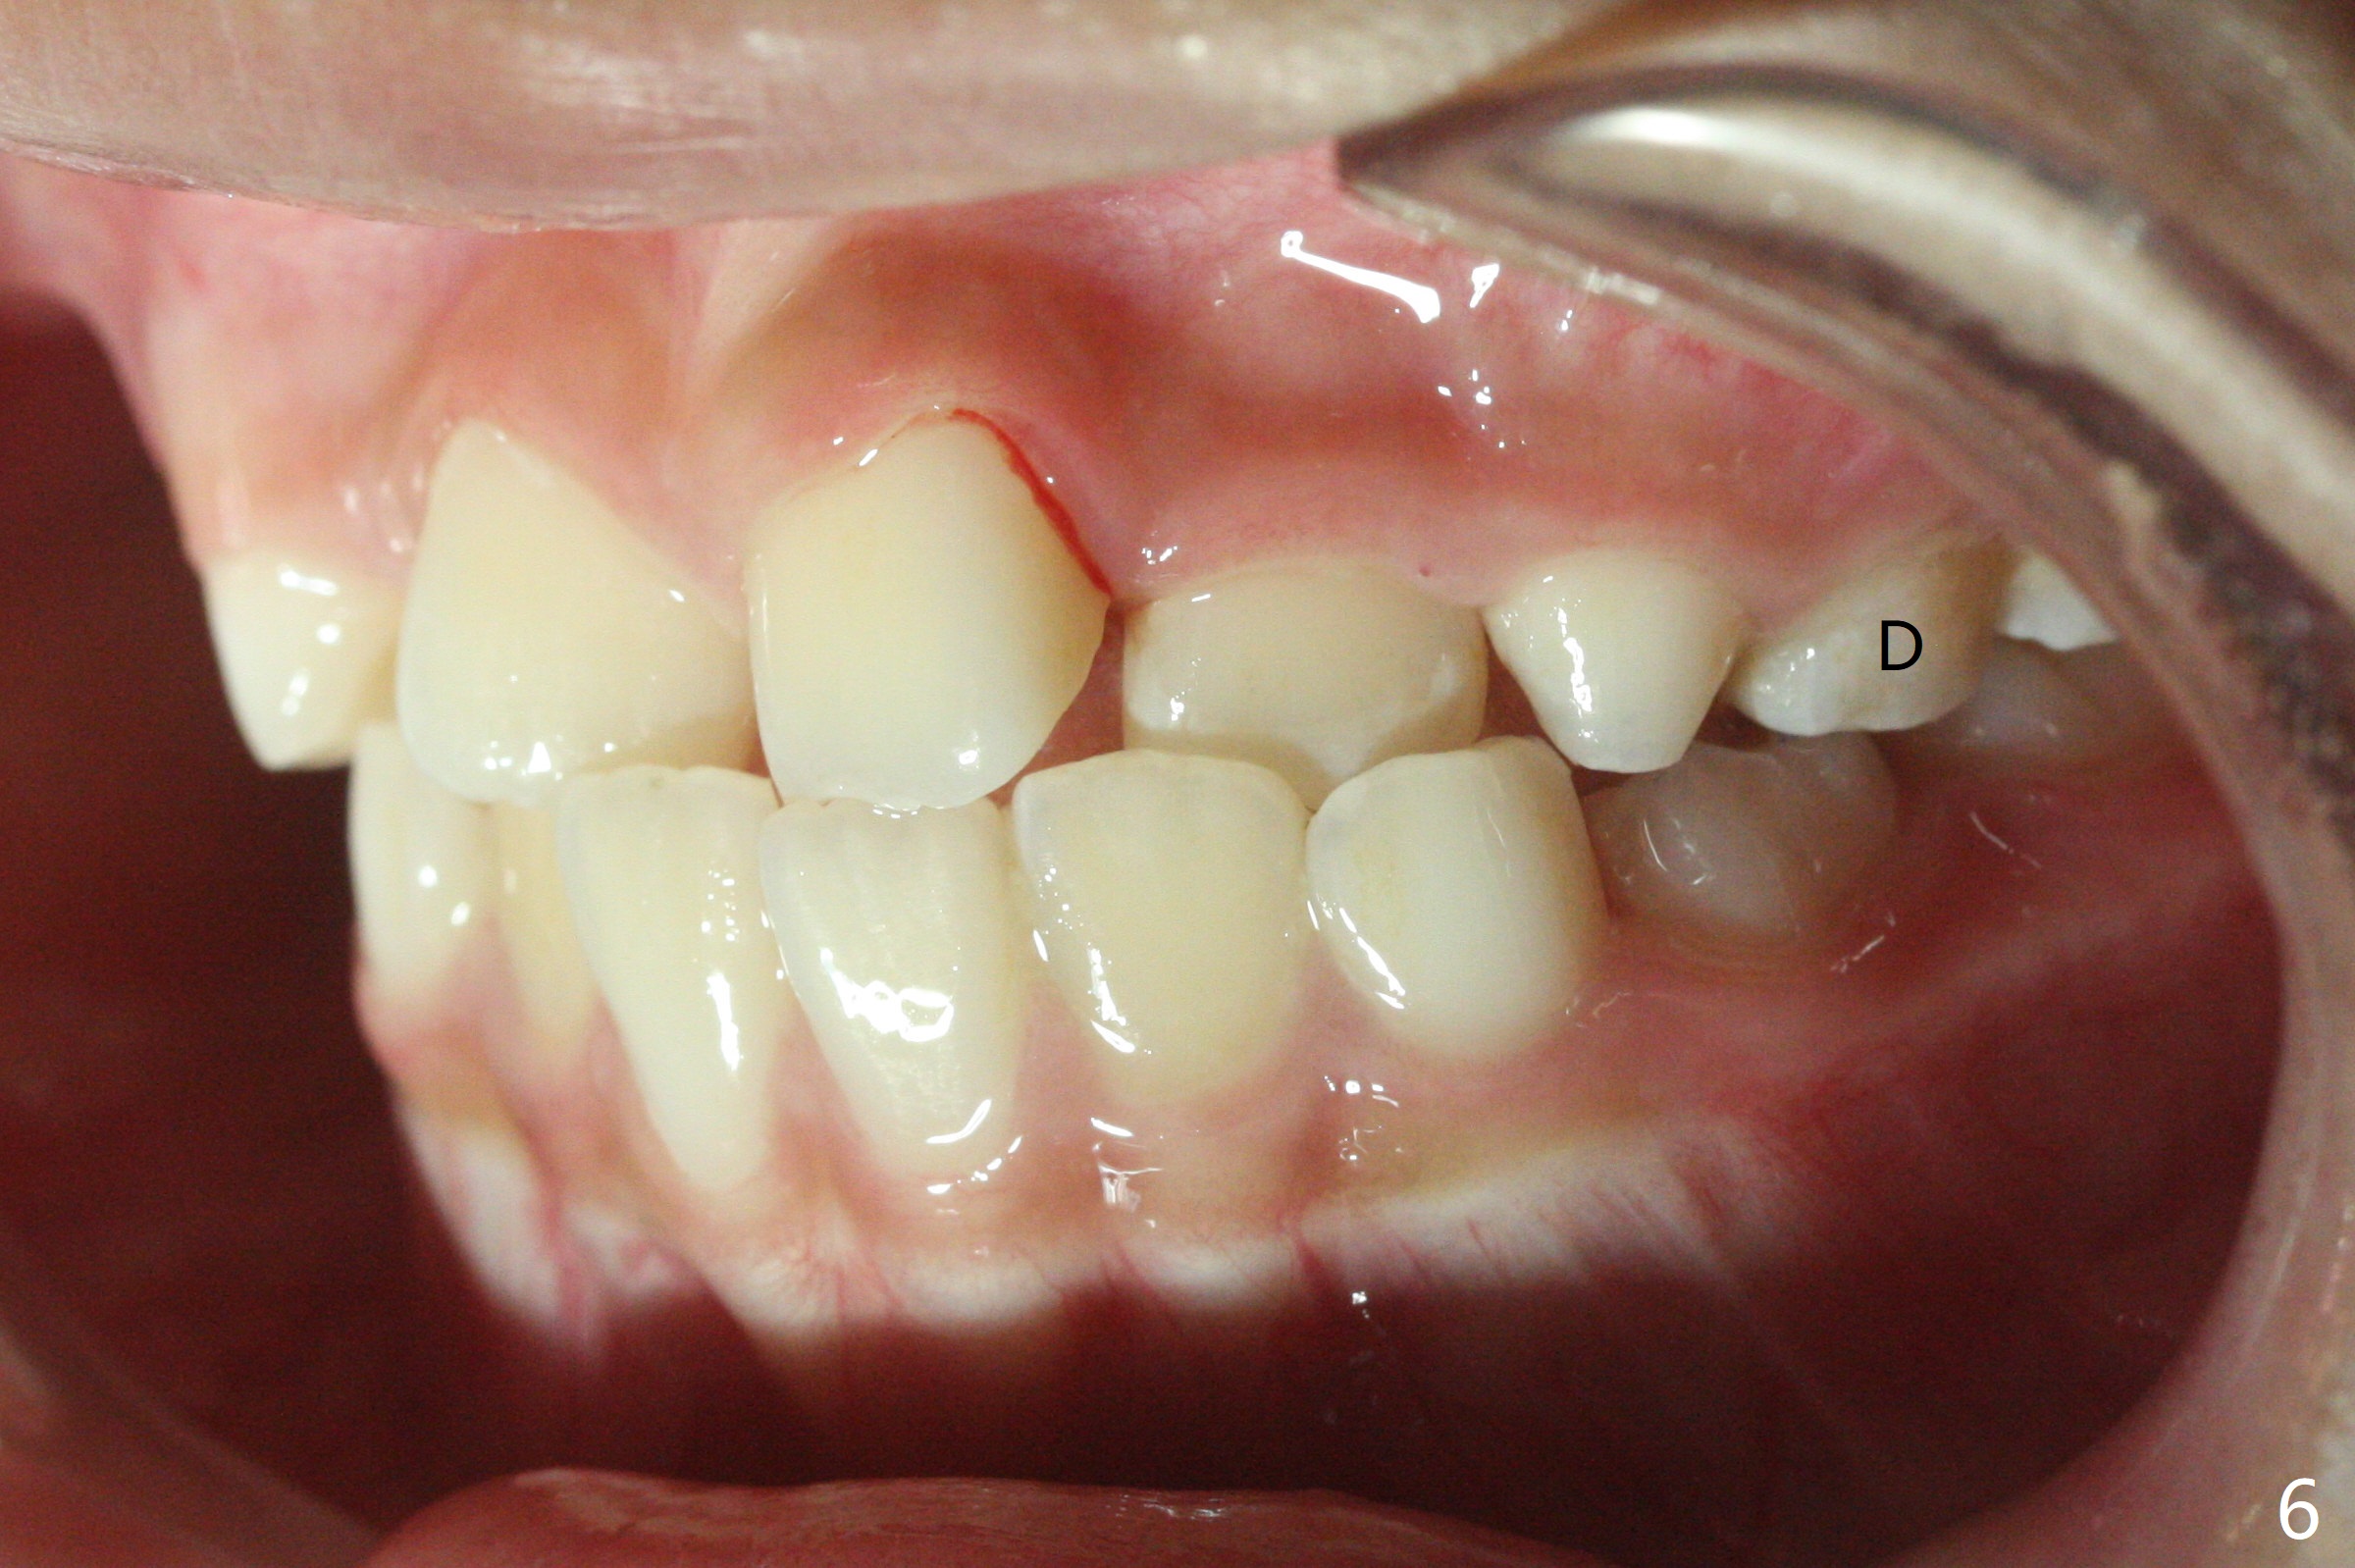

7岁女孩龋齿(图一)到八岁发展的严重(图二,三 (D))。为了有完整支抗,利用树脂(而不是不锈钢牙冠)保留左上第一乳磨牙(图六:D),以后可以安置矫正器。面部匀称(图七至十)。乳尖牙,第一恒磨牙:第一类咬合(图十一,十二)。左上前牙拥挤比右边轻,因为左上D龋齿破坏(图十三:D)。前牙扩弓时,右上D近中需要片切(^)。下颌拥挤轻(图十四),矫正器可以迟放置。